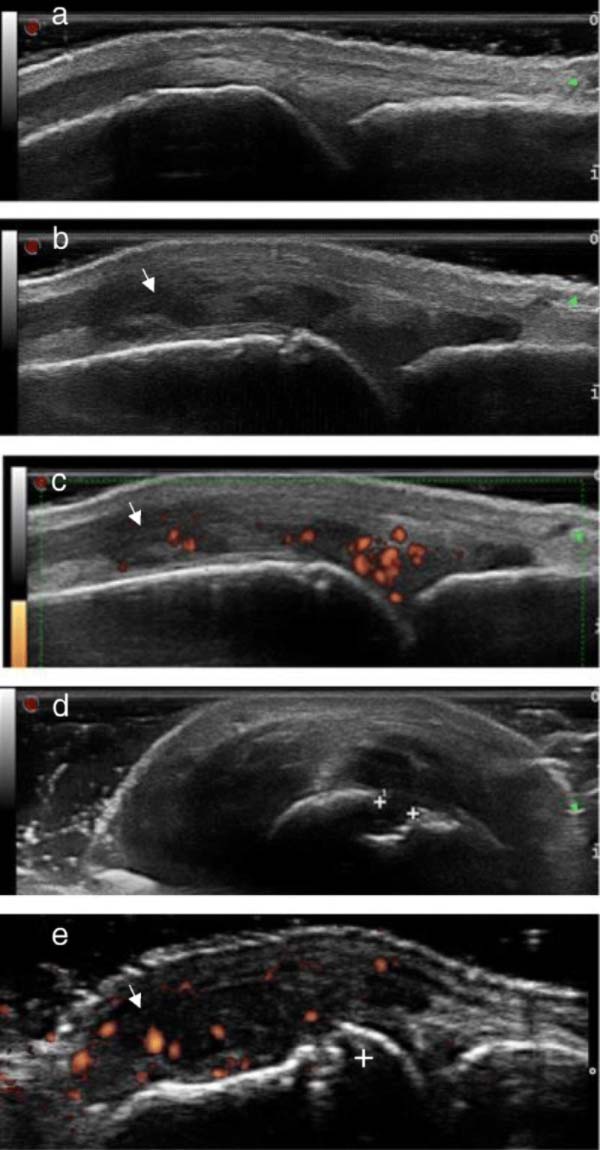

Siêu âm sử dụng sóng âm tần số cao để tạo ra hình ảnh các cơ quan và mô trong cơ thể. Bác sĩ sẽ bôi một lớp gel mỏng lên da, sau đó đặt đầu dò lên vùng cơ thể (tùy bộ phận bị ảnh hưởng). Đầu dò chuyển đổi dòng điện thành sóng âm tần số cao và truyền vào cơ thể. Sóng âm dội lại từ cấu trúc bên trong và trở lại đầu dò. Đầu dò chuyển sóng thành tín hiệu điện. Máy tính sẽ chuyển tín hiệu điện thành hình ảnh, video.

Sóng siêu âm có thể dùng để chẩn đoán các vấn đề về xương khớp: